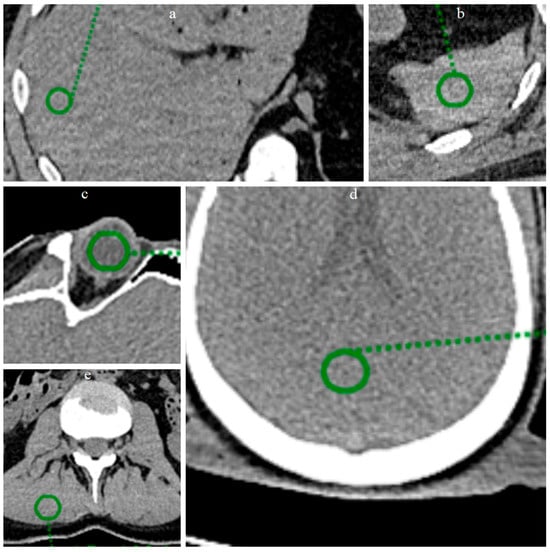

In the present study, a quantitative noise analysis was also performed by applying circular regions of interest (ROI) (radius 8 mm) at five anatomical locations (Figure 3): vitreous body, brain parenchyma, liver parenchyma, splenic parenchyma and paravertebral muscle. Within each ROI, the mean and standard deviation (SD) of the attenuation values (Hounsfield units) were calculated in order to characterize and compare the noise level before and after processing with ErisNet.

Figure 3.

ROI placement at five anatomical locations for quantitative analysis. Circular green ROIs with radius 8 mm were positioned on: (a) liver parenchyma, (b) splenic parenchyma, (c) vitreous body of the eye, (d) brain parenchyma, and (e) lumbar paravertebral muscle. These anatomical regions were selected to evaluate ErisNet performance across different tissue types and attenuation characteristics.